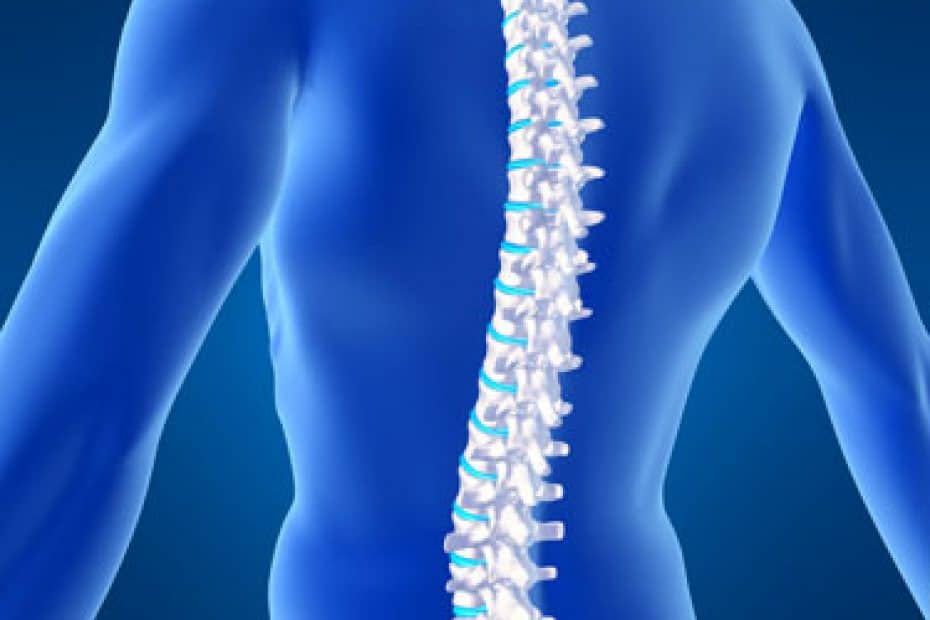

Especialidade: Neurocirurgia é uma área da medicina que se dedica ao diagnóstico e tratamento de doenças do sistema nervoso central e periférico, por meio de procedimentos cirúrgicos. Os neurocirurgiões são especialistas em tratar condições como tumores cerebrais, aneurismas, lesões na medula espinhal, epilepsia, entre outras. O Instituto Amato é um hospital dia em São Paulo que oferece procedimentos cirúrgicos minimamente invasivos em diversas especialidades, incluindo a neurocirurgia.